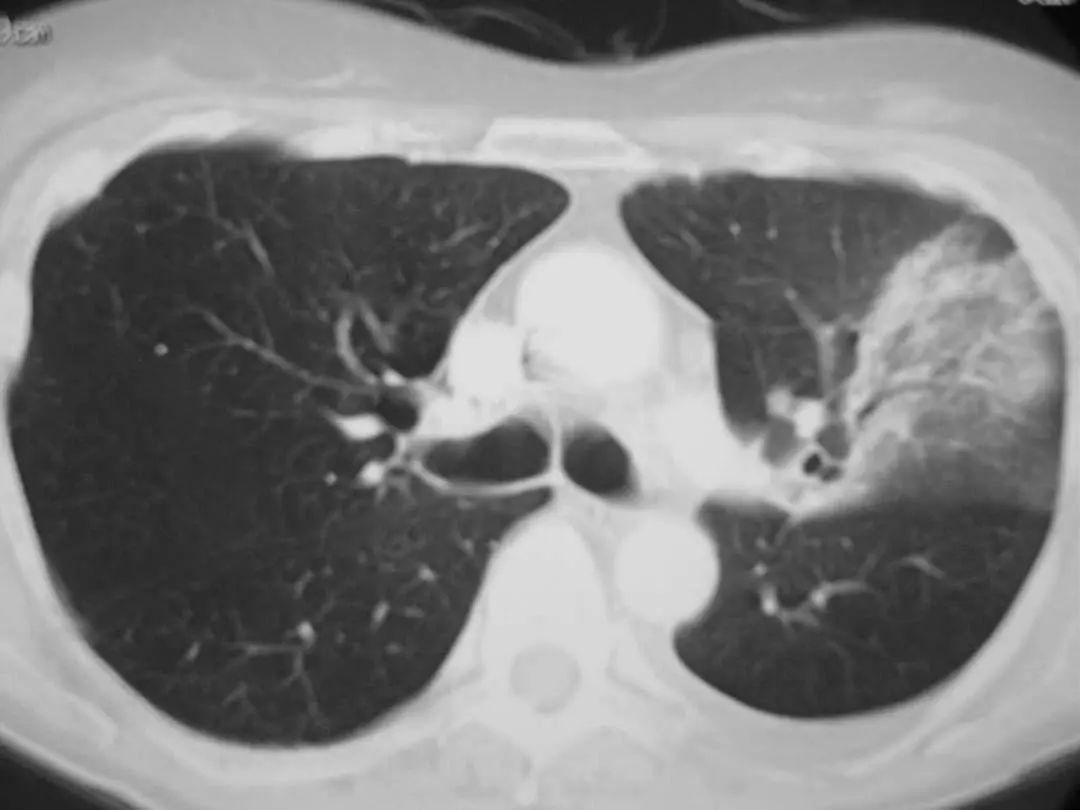

图1.7 CT扫描显示左下叶模糊的气腔浸润。

图1.8 45岁的衣原体肺炎患者的胸部CT扫描显示右上叶浸润。